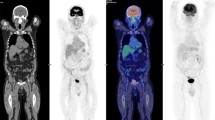

In average, (2.4 ± 0.1) MBq per kg bodyweight (range: 2.3–2.5 MBq/kg) were injected. Organs showed in general low uptakes, see Fig. 2a, while the renal cortices were clearly visible with a SUV of in average (8.6 ± 2.3) after 30 min (average of all left and right kidneys), which slowly dropped over time until a SUV of (1.3 ± 0.2) after the full examination time of 270 min. All according time activity curves including heart are presented in Fig. 2b.

Dynamic series of static images of [18F]Me4FDG. a: dynamic series of static images of [18F]Me4FDG showing the biodistribution of this tracer. The first image represents a sum of the first 30 min. b: dynamic uptake behavior, with the renal parenchyma showing the highest uptake at the beginning of the tracer injection. Mean SUV of all referring regions is shown. SUV: standardized uptake value

In Fig. 3, the dose of [18F]Me4FDG from one representative female subject is shown 270 min after injection. The calculated effective dose was in total (0.013 ± 0.003) mSv/MBq. The organs with the highest absorbed dose were the kidneys with 0.05 mSv/MBq per kidney while the brain showed almost no uptake, see Fig. 3; Table 2. After 60 min, 12 ± 15% of the administered dose was excreted into the bladder. For the individual uptake of all organs that had visible tracer uptake, see Table 2.

Biodistribution of [18F]Me4FDG. Left: Fused PET/CT image of the last scan at 270 min showing the biodistribution of [18F]Me4FDG with the highest concentration measured in the renal cortices. Middle: Dose map in units of mSv of the same individual. Right: Transaxial view of the kidneys in the PET images, the low dose CT images as well as the fused scans